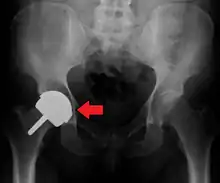

Metal sensitivity

Concerns are being raised about the metal sensitivity and potential dangers of metal particulate debris. New publications[26][27] have demonstrated development of pseudotumors, soft tissue masses containing necrotic tissue, around the hip joint. It appears these masses are more common in women and these patients show a higher level of iron in the blood. The cause is unknown and is probably multifactorial. There may be a toxic reaction to an excess of particulate metal wear debris or a hypersensitivity reaction to a normal amount of metal debris.

Metal hypersensitivity is a well-established phenomenon and is common, affecting about 10–15% of the population.[28] Contact with metals can cause immune reactions such as skin hives, eczema, redness and itching. Although little is known about the short- and long-term pharmacodynamics and bioavailability of circulating metal degradation products in vivo, there have been many reports of immunologic type responses temporally associated with implantation of metal components. Individual case reports link hypersensitivity immune reactions with adverse performance of metallic clinical cardiovascular, orthopedic and plastic surgical and dental implants.[28]

Metal toxicity

Most hip replacements consist of cobalt and chromium alloys, or titanium. Stainless steel is no longer used. All implants release their constituent ions into the blood. Typically these are excreted in the urine, but in certain individuals the ions can accumulate in the body. In implants which involve metal-on-metal contact, microscopic fragments of cobalt and chromium can be absorbed into the person's bloodstream. There are reports of cobalt toxicity with hip replacement, particularly metal-on-metal hip replacements, which are no longer in use.[29][30]